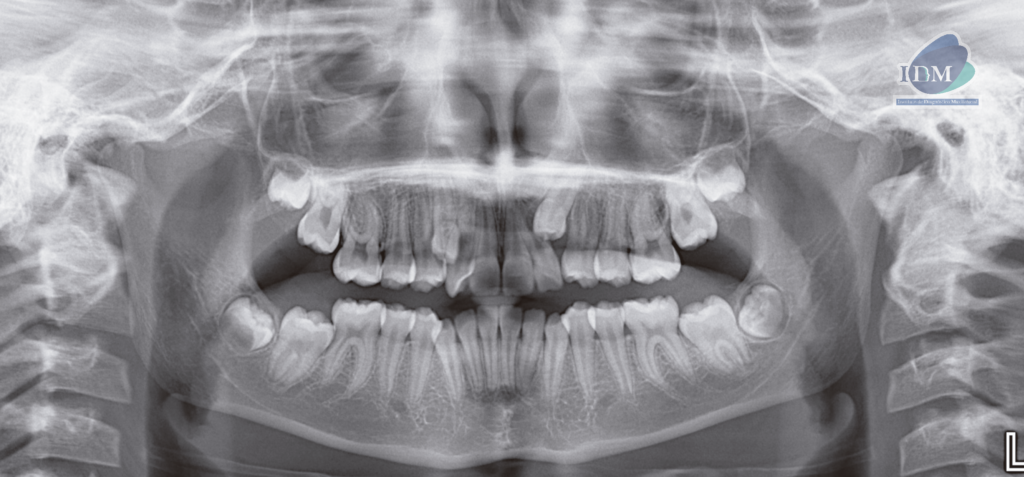

A la evaluación de la radiografía panorámica se observa terceras molares en evolución intraósea, piezas dentarias 18 y 28 en evolución extraósea y distoanguladas; piezas 37 y 47 en evolución extraósea y mesioanguladas; asimismo se observa la 13 en evolución extraósea en posición ectópica y la pieza 23 mesioangulada e impactada.

Radiografia Panorámica